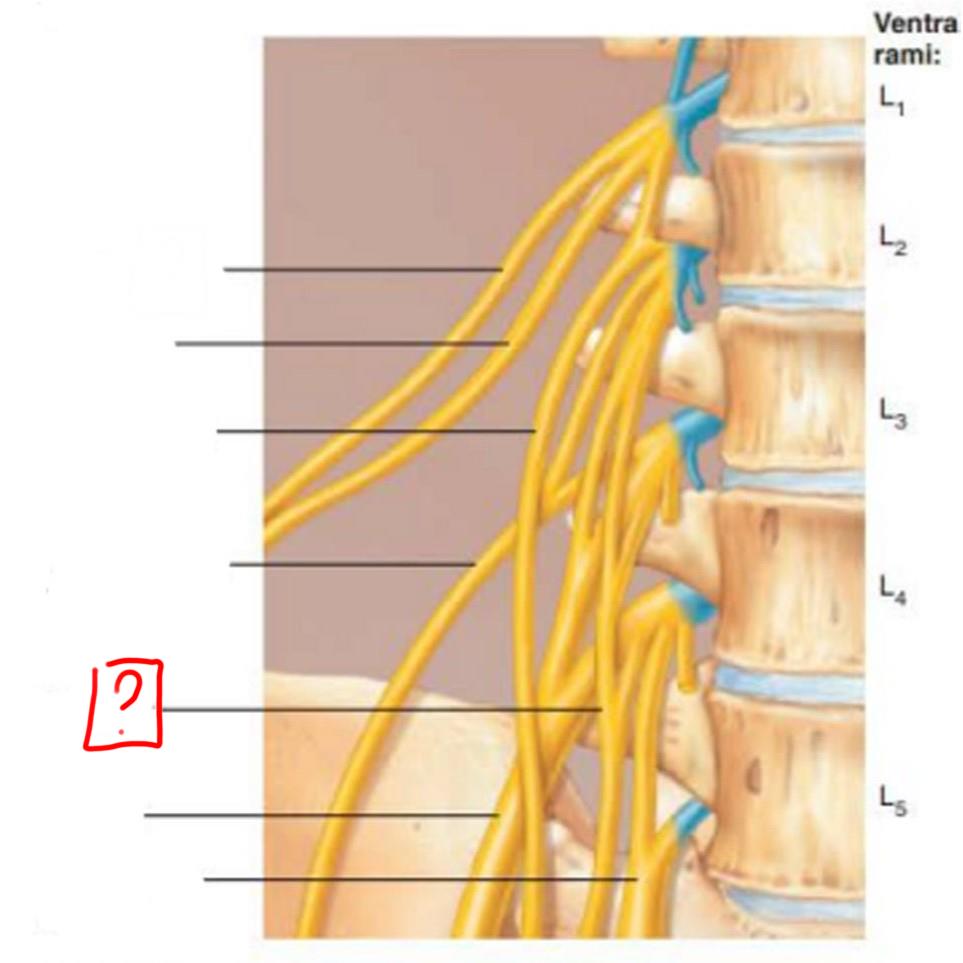

lumbar plexus

L1-L4

major nerves: ilioinguinal, obturator, femoral, genitofemoral

iliohypogastric

ilioinguinal

genitofemoral

lateral femoral cutaneous

obturator

femoral

lumbosacral trunk